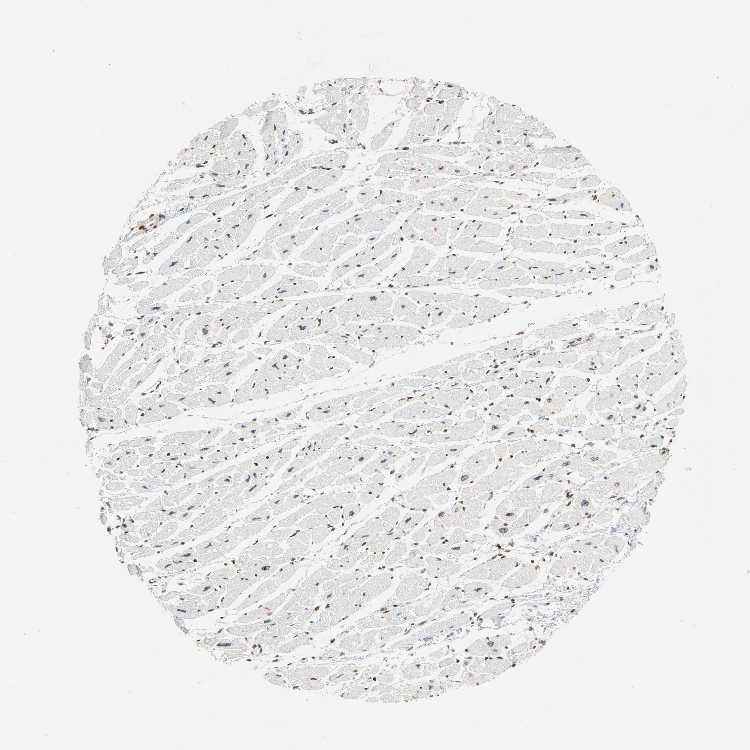

TISSUE PRIMARY DATA HEART MUSCLE Show tissue menu

HEART MUSCLE - Antibody stainingi

Antibody staining in the annotated cell types in the current human tissue is reported as not detected, low, medium, or high, based on conventional immunohistochemistry profiling in selected tissues. This score is based on the combination of the staining intensity and fraction of stained cells.

Each image is clickable and will lead to virtual microscopy that enables deeper exploration of all samples and also displays staining intensity scores, fraction scores and subcellular localization as well as patient and tissue information for each sample.

Antibody HPA004246Antibody CAB018641

Cardiomyocytes MediumMedium